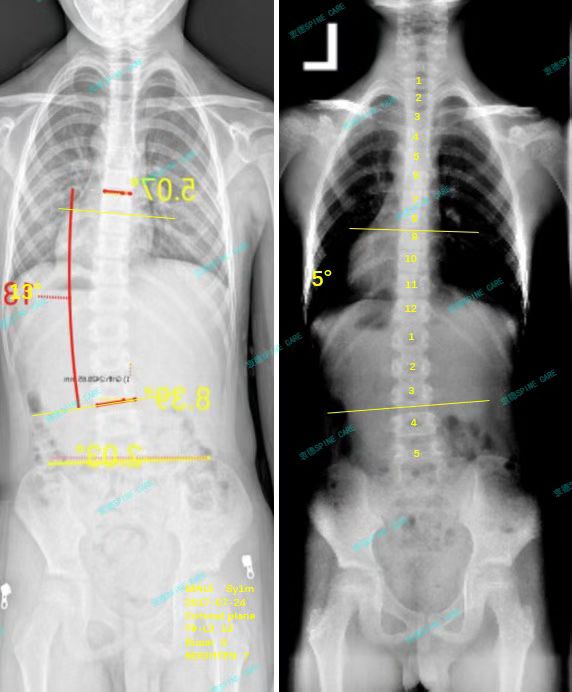

衷德脊柱,我们只关注侧弯保守治疗~

Zhongde Spine, bending no breaking ~